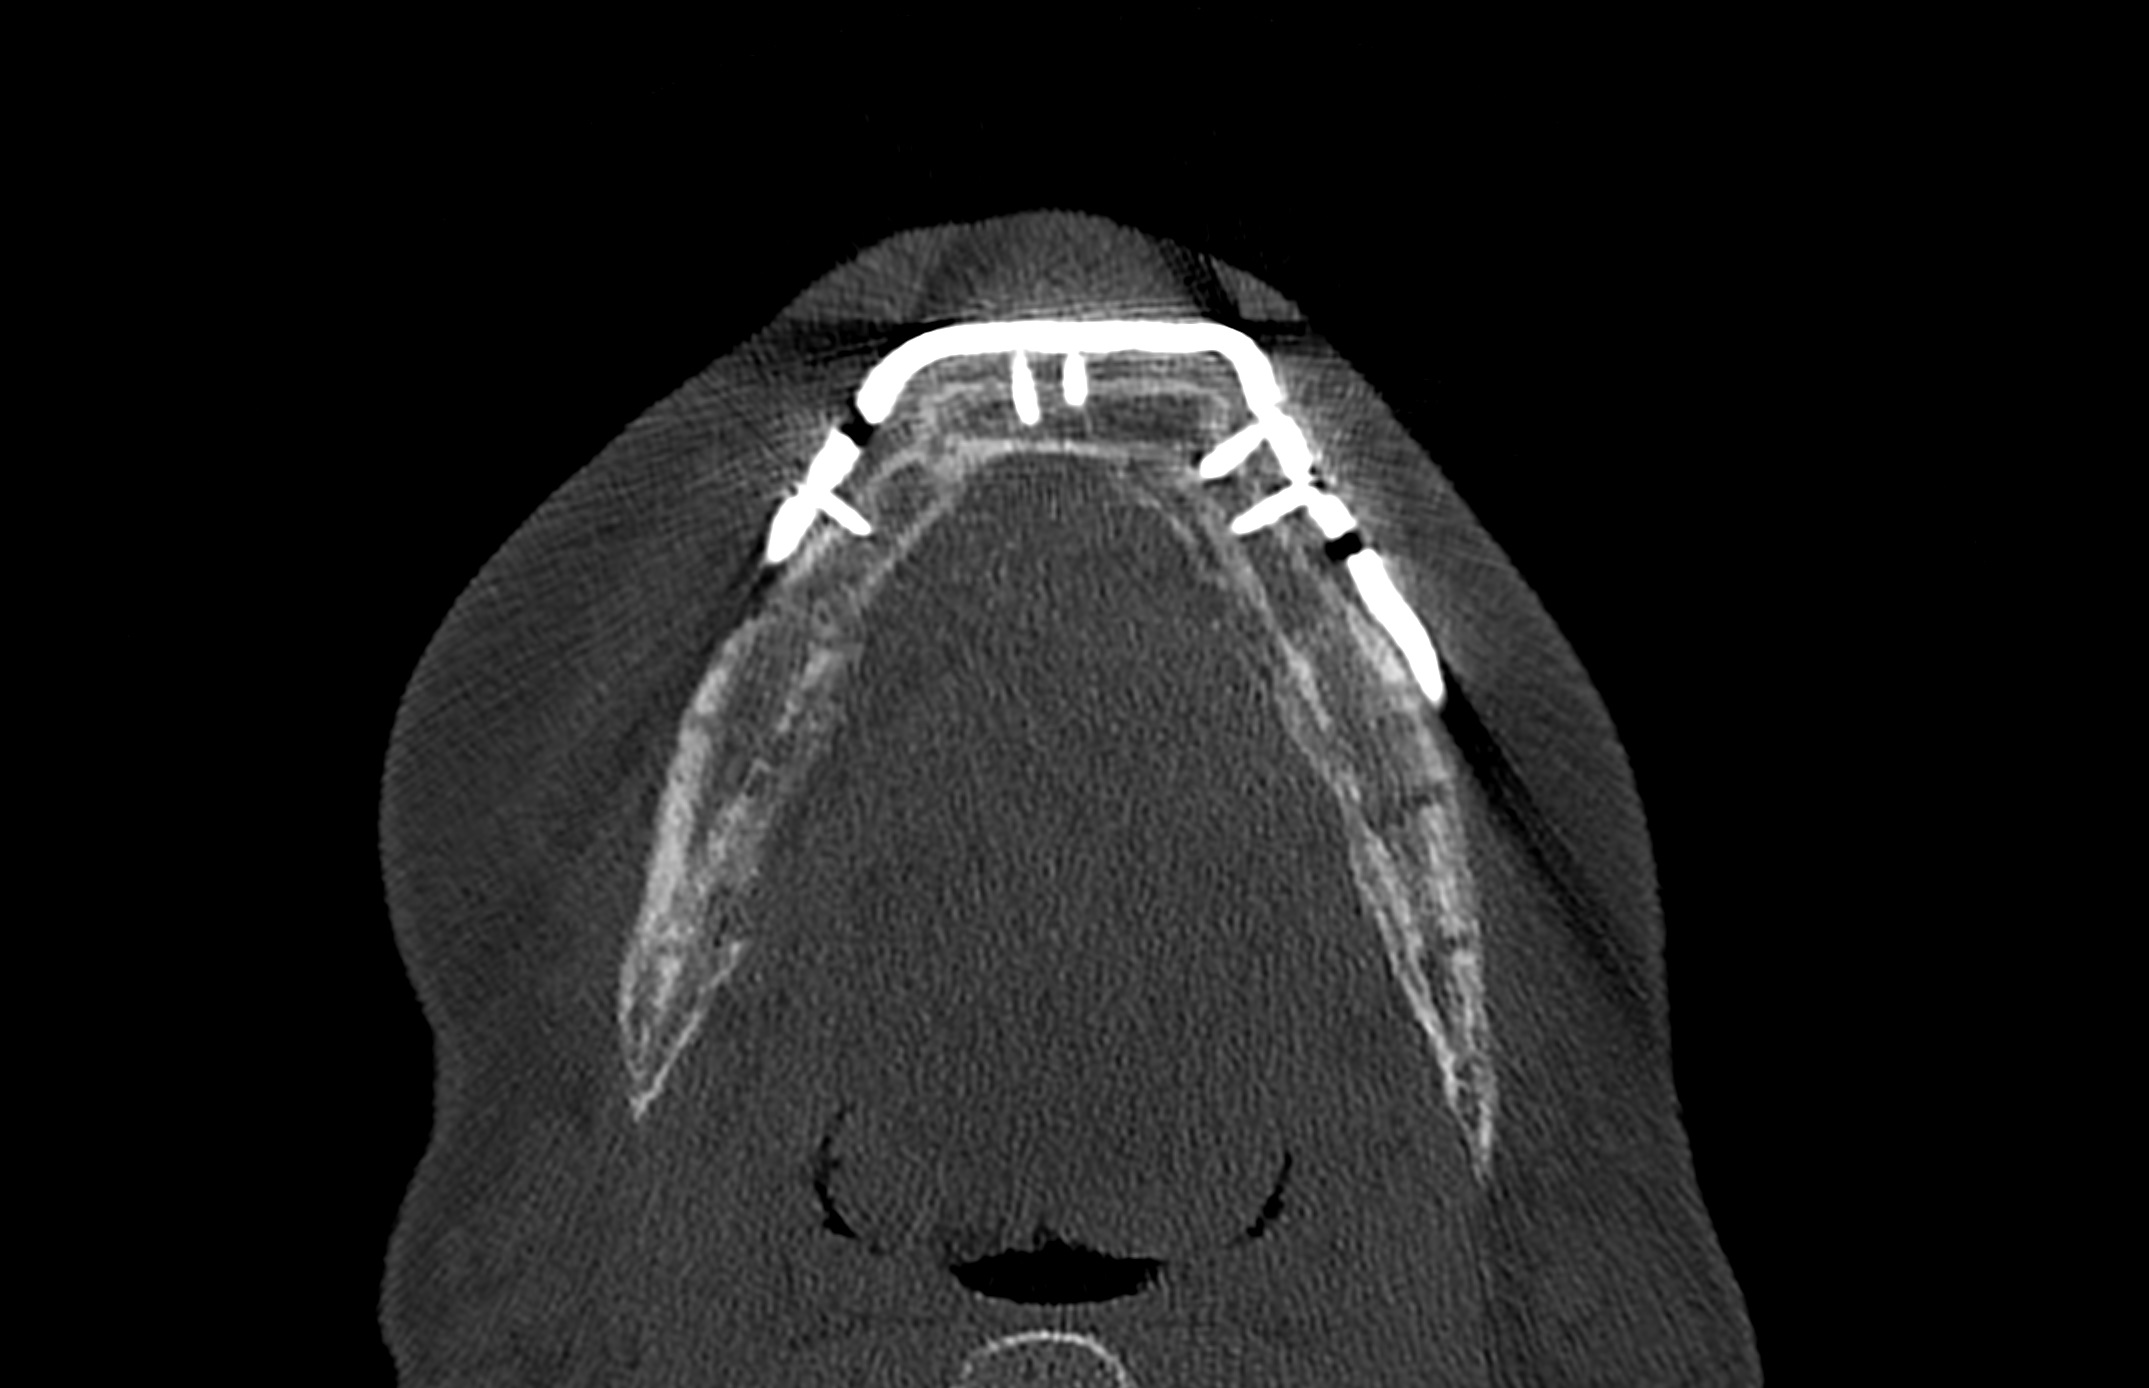

Postoperative imaging confirmed minimal intersegmental gaps to the mandibular remnants with undisturbed healing but limited overall bone volume (Fig. 7a-c). Therefore removal of the PSPMP and a preimplantological augmentation with corticocancellous iliac bone grafts followed 16 months later.

Finally, dental implants were inserted (Fig. 8).